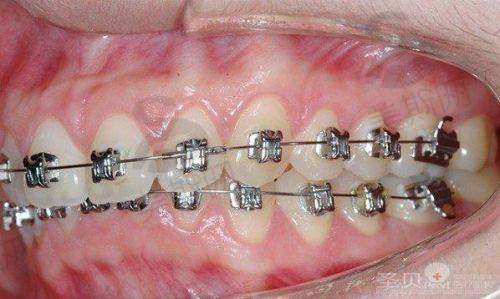

2. 牙齿矫正:涵盖隐形矫正、传统金属托槽矫正、陶瓷自锁托槽矫正、舌侧矫正,特色技术为隐适美iTero口内扫描,3分钟即可生成矫正方案,预知矫正成效,隐形矫正病例累计超3000例。

“23岁女生,因为牙齿不齐一直特别自卑,在壹颗芽做了隐适美矫正。李医生用iTero扫描仪给我扫了牙,3分钟就看到了矫正后的成效动画,太神奇了!矫正过程戴了32副牙套,每两周换一副,平时摘戴方便,不影响吃饭和约会。现在矫正10个月,牙齿已经排齐了,侧脸线条都变好看了!总共花了32000元,中间还送了2次洁牙,性价比特别高。更感动的是医生每次复诊都耐心调整方案,还会提醒我注意事项,现在朋友都夸我笑起来更自信了!”